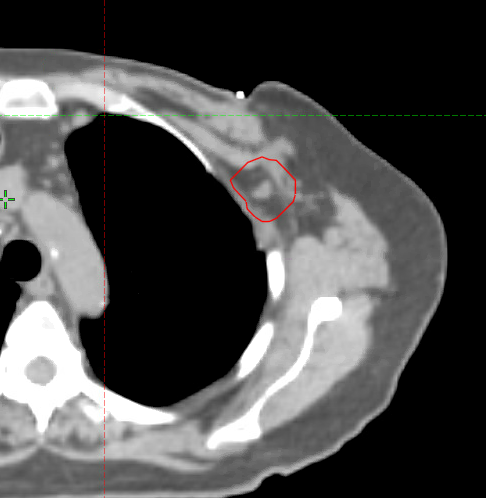

Thanks, no scar boost, and no expander. Basically just want to boost the red volume. Am wondering if chest wall proximity is problematic as well.

Basically just want to boost the red volume. Am wondering if chest wall proximity is problematic as well.

Chest wall proximity will not be an issue. What dose were you planning to give? Peripheral T3 NSCLCs get 60 + Gy and I have never seen toxicity.

OK, I guess. I'd have to scroll through the CT myself, but usually the ones that are truly 'unresectable' and co-planar with vessels or buried deep in level 3. That seems like on the level 1/2 border.... I would still try to biopsy - you may be able to bring it back to the surgeon if a biopsy is positive.